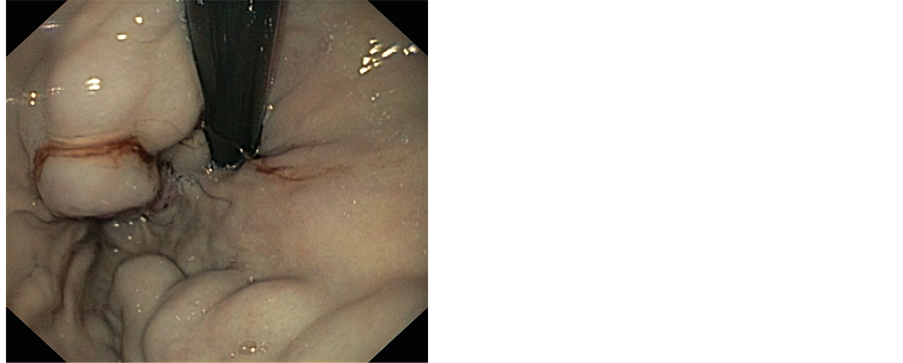

An endoscopy was performed 24 hours after the bleeding period and had objectified stage I of esophageal varices with some red signs associated with two large varices with red signs in cardia, the patient had received an injection of a chemical glue 1cc at the gastric varices without maternal neither fetal incident. An abdominopelvic ultrasound was performed and showed signs of portal hypertension and signs of chronic liver disease with progressive singleton pregnancy. The evolution was marked by a smooth pregnancy and delivery at term vaginally of a newborn male, birth weight 3000 g, APGAR 10/10 with good psychomotor development. Nine months later, the patient presented bleeding. An upper endoscopy showed a varicose vein in the cardia, which was treated by histoacryl of injection (Figures 1 and 2).

Figure 1. Gastric varices.